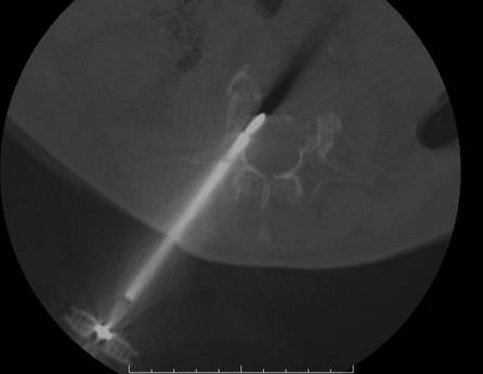

Il 10 febbraio scorso, il portale informativo online "Cannizzaro Salute" riportava la notizia, ripresa dall'agenzia Italpress e dal Corriere del Mezzogiorno online (Leggi su Guidasicilia.it), dell'esecuzione di un intervento di "distruzione di un tumore vertebrale con il calore e contestuale ricostruzione dell’osso mancante con un polimero", in anestesia locale, ad opera dell'équipe del dottor Manfré. La procedura, spiegava la nota, "si basa sulla radioablazione, ovvero sulla distruzione del tumore, sia esso primitivo o metastatico, attraverso il calore emanato da uno speciale elettrodo, introdotto in una cannula inserita nella vertebra". Secondo quanto dichiarato dal Cannizzaro, era il "primo intervento (di questo tipo ndr) in Italia, e fra i primi in Europa dopo quelli in Germania".

Ora, se a generare la contesa sia stato quel suffisso diverso - nel primo caso si parlava di radioablazione, nel secondo di termoablazione - non è dato, almeno ai giornalisti, saperlo con certezza. Sta di fatto che, dopo la pubblicazione di un secondo articolo in cui si approfondiva ulteriormente la tematica, Manfré interveniva nuovamente, segnalando che Basile, dal suo punto di vista, aveva confuso la "radio ablazione dei tessuti molli vertebrali - tecnica in uso da decenni nei vari presidi ospedalieri, che tratta tumori esterni al corpo vertebrale - con l'innovativa procedura eseguita al Cannizzaro, che riguarda, viceversa, tumori localizzati in sede intravertebrale, cioè all'interno del corpo vertebrale".